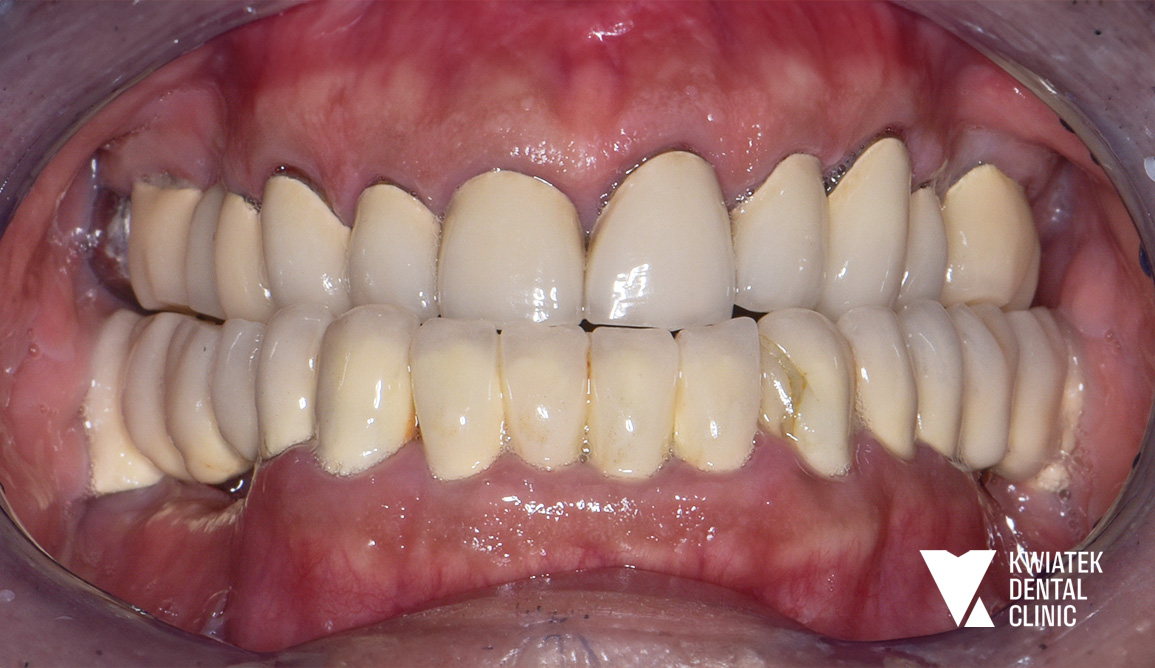

Pełna rekonstrukcja zwarcia i estetyki - historia wymagającej metamorfozy

Pacjent zgłosił się do kliniki z zaawansowanymi problemami stomatologicznymi: licznymi ubytkami próchnicowymi, brakami zębowymi, starciem zębów oraz zaburzeniami zwarcia. Leczenie obejmowało kompleksową diagnostykę, leczenie zachowawcze i endodontyczne, zabiegi chirurgiczne, implantację oraz wieloetapową odbudowę protetyczną. Efektem terapii jest perfekcyjnie zbalansowany zgryz, najwyższy komfort funkcjonowania oraz naturalnie piękny uśmiech, który podkreśla indywidualny charakter pacjenta i pozwala mu w pełni cieszyć się nim każdego dnia.